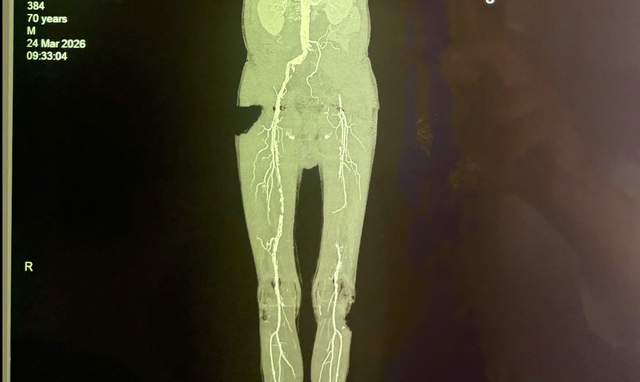

Hình ảnh chẩn mạch chi của bệnh nhân bị tắc nhiều đoạn có nguy cơ gây biến chứng hoại tử, cưa chân

Qua thăm khám lâm sàng, các bác sĩ ghi nhận động mạch đùi, động mạch khoeo và động mạch dưới gối chân bên trái của bệnh nhân không bắt được. Kết quả siêu âm Doppler mạch máu chi dưới ghi nhận tắc động mạch chậu bên trái, mất phổ 3 pha động mạch đùi, khoeo chân trái. Bệnh nhân được chụp cắt lớp vi tính mạch máu chi dưới (CTA) để đánh giá cụ thể và chính xác hơn tình trạng bệnh lý mạch máu, vị trí tắc nghẽn, mức độ tổn thương mạch máu.

Kết quả cho thấy bệnh nhân bị tắc động mạch chậu bên trái, tắc 1/3 giữa động mạch đùi bên trái và xơ vữa rải rác các động mạch chi dưới khác.